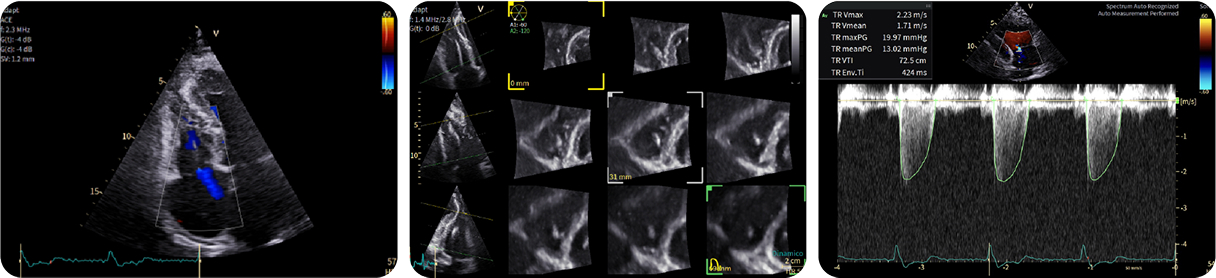

Casi clinici

Scopri come le tecnologie di imaging più innovative di GE HealthCare hanno giocato un ruolo chiave nella diagnosi di condizioni cardiache complesse.